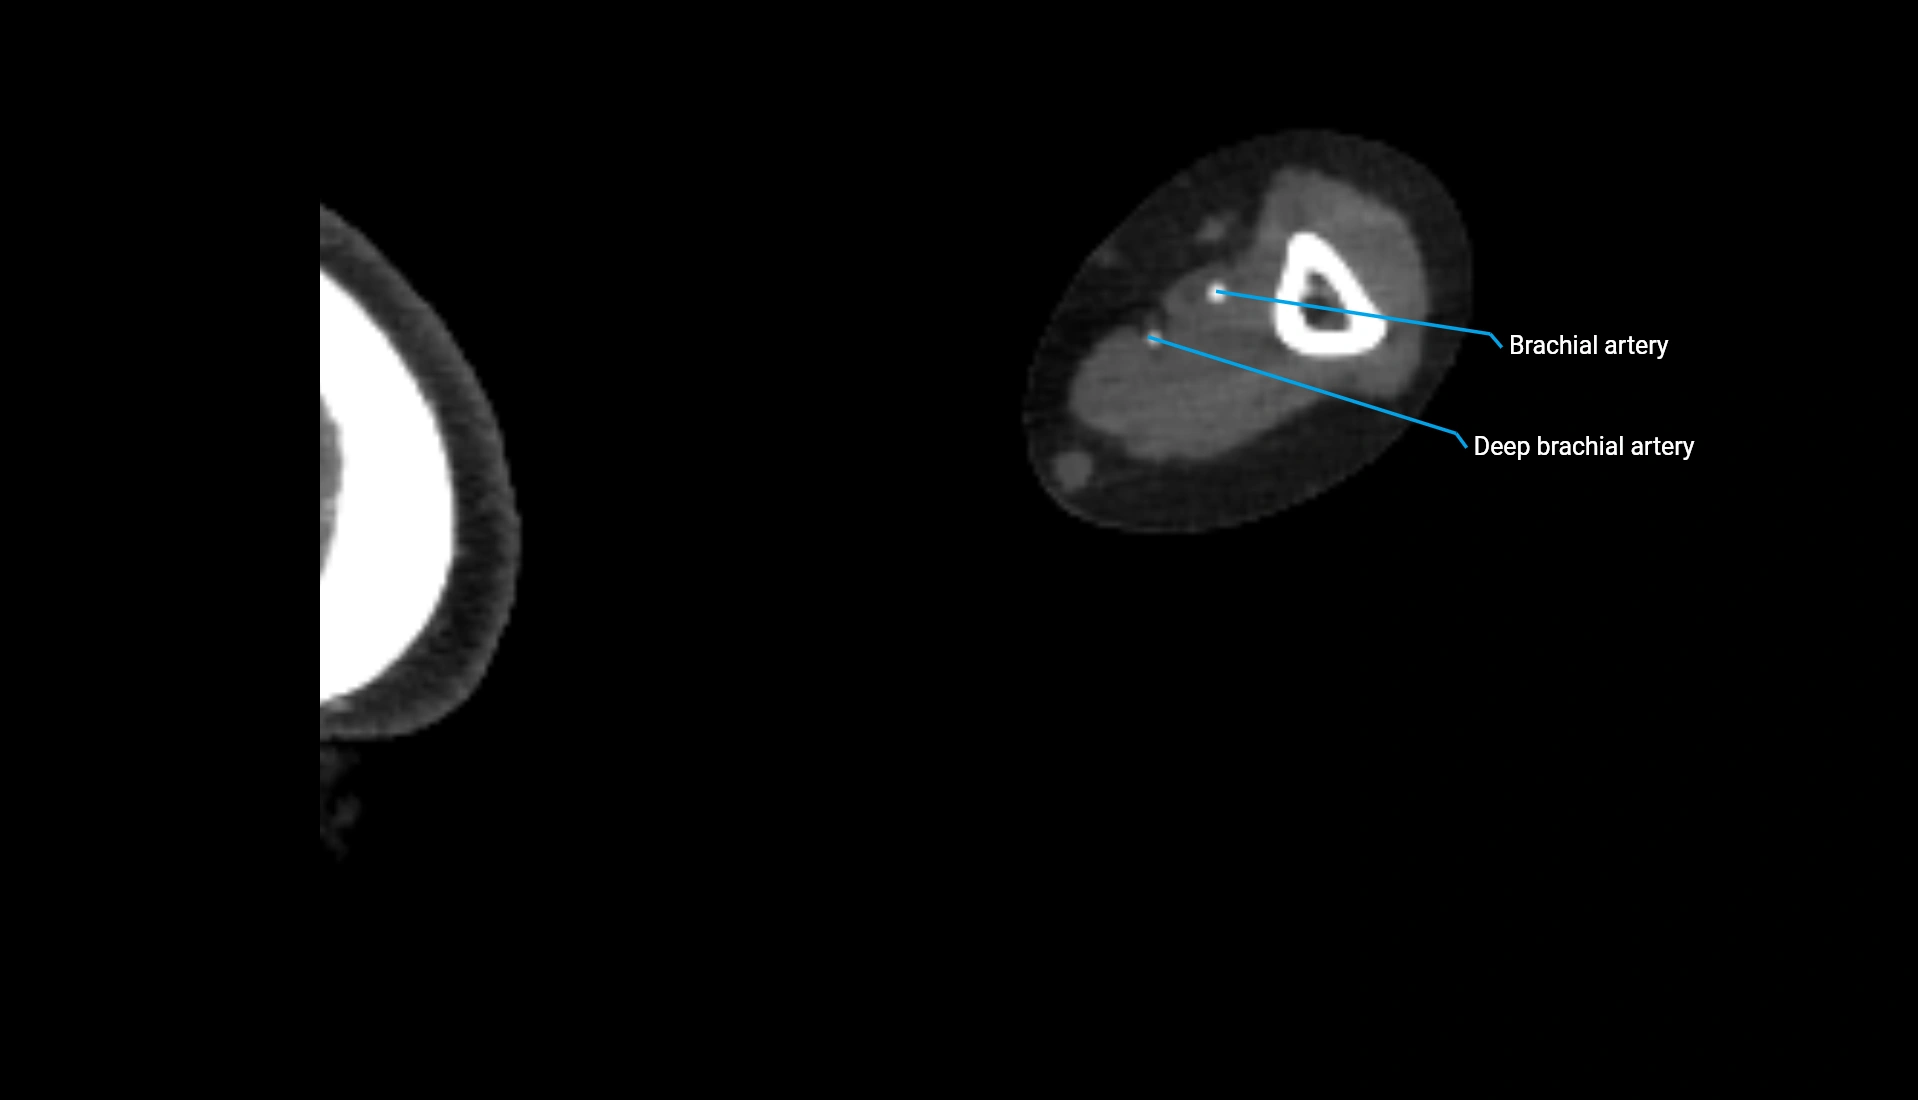

CT Appearance

Non-Contrast CT:

• Cortex: High-density, sharply defined

• Subchondral bone: Dense cancellous matrix

• Articular surface: Smooth concave contour articulating with the capitellum

• Excellent for evaluating bone integrity, alignment, and subtle fractures